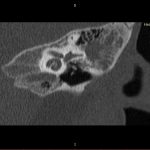

- Diagnosticul edemului cerebral, a contuziei cerebrale, a leziunilor axonale difuze edematoase/hemoragice, a dilacerării cerebrale, a hematomului intraparenchimatos posttraumatic, a hematoamelor subdurale/extradurale (acute, subacute, cronice), a hemoragiei intraventriculare, a hemoragiei subarahnoidiene

- Diagnosticul traumatismelor de bază de craniu

- Diagnosticul fracturilor:

- Cu înfundare

- Complexe cranio-sinusale

- Complexe cranio-etmoidale

- Complexe cranio-orbitare

- Complexe cranio-faciale